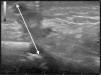

The patient was a 32-year-old man with no past history of interest. He was seen in dermatology outpatients for a tumor in the form of a cutaneous horn sunken into the skin over the left horizontal ramus of the mandible (Fig. 1). Examination revealed no alterations of the oral cavity. The patient stated that the region was tender. He had applied topical treatment with 2% mupirocin ointment without improvement. B mode skin ultrasound (Esaote, Genoa, Italy) using an 18MHz probe revealed a slightly tortuous, relatively well-defined, hypoechoic linear structure that extended to the surface of the cortical bone of the mandible (Fig. 2). Doppler study showed blood vessels in the area around the tract, suggestive of inflammation, and a poorly defined hypoechoic outline in B mode (Fig. 3). With a diagnosis of cutaneous odontogenic sinus, the patient was referred to the maxillofacial surgery department, where the study was completed with orthopantomography. This x-ray study revealed a radiolucent image that surrounded the apex of the posterior root of the left first molar (Fig. 4). Conservative treatment was performed with endodontia and restoration with an amalgam filling, leading to resolution of the cutaneous sinus in 20 days.

Recently, Shobatake et al.5 published 3 cases of cutaneous odontogenic sinuses diagnosed by ultrasound. Dermatologic ultrasound shows a well-recognized pattern with a relatively well-defined, linear but slightly tortuous, hypoechoic sinus tract that is seen to reach the surface of the cortical bone; Doppler reveals a variable degree of vascularization. Ultrasound is a tool that complements other radiologic techniques and requires little time to perform. It is an excellent option to facilitate the diagnosis of this type of lesion, even for dermatologists with little experience in the management of oral pathology. In addition, it can be used to monitor therapy and to evaluate the associated inflammation to help determine a possible indication for antibiotic prophylaxis prior to intervention.